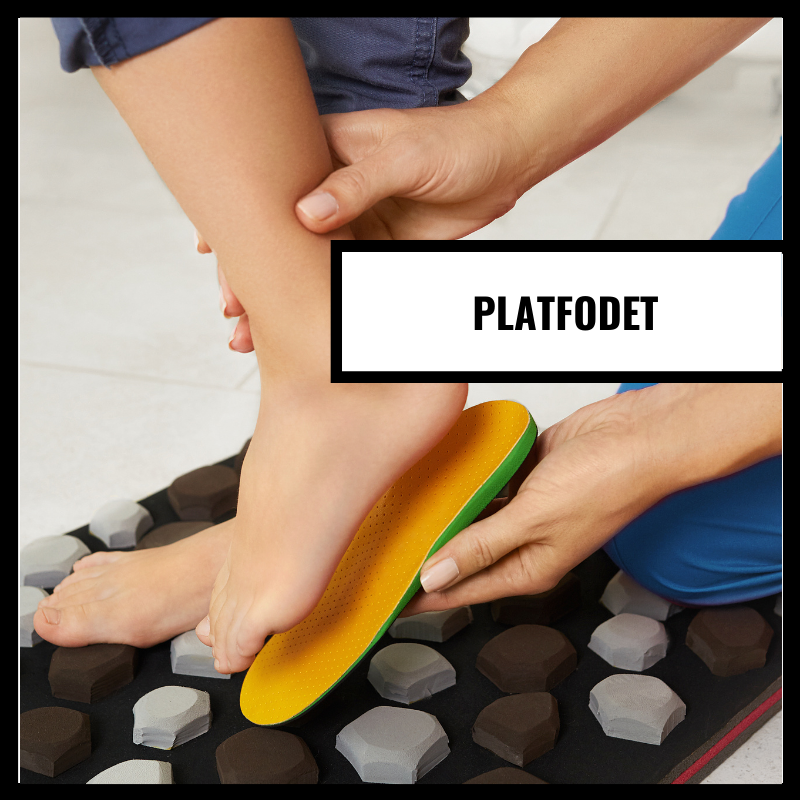

Hvis du er platfodet er det vigtigt, du vælger de rigtige sko Se her

Hvis du er platfodet er det vigtigt, du vælger de rigtige sko Se her

Platfod hos børn: Hvad er det, og kan - Børnenes

Platfod hos børn: Hvad er det, og kan - Børnenes

Platfod → Hvad er det hvordan opstår det? Få svaret her!

Platfod → Hvad er det hvordan opstår det? Få svaret her!

Platfod hos børn - på sundhed.dk

Platfod hos børn - på sundhed.dk

Platfod indlæg | Book tid til fødder og få en fodanalyse

Platfod indlæg | Book tid til fødder og få en fodanalyse

Hvad platfod? | Indlægsspecialisten

Hvad platfod? | Indlægsspecialisten

Platfod indlæg - Hvad er platfod? - Alt hvad skal vide!

Platfod indlæg - Hvad er platfod? - Alt hvad skal vide!